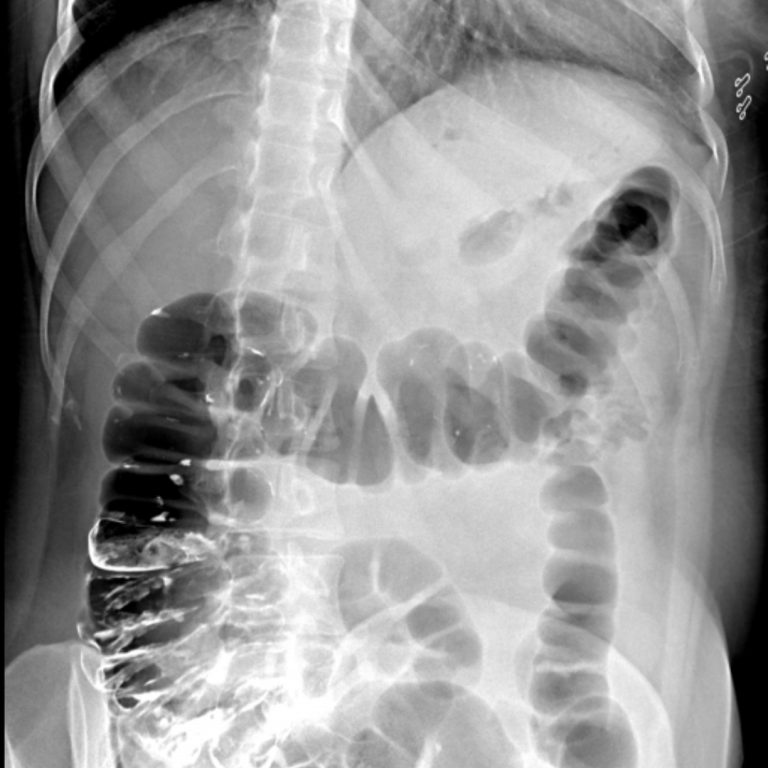

İNCE BARSAK GRAFİSİ

İnce barsakların kontrast madde içirilmesi (ince barsak pasaj grafisi) veya hastaya yutturulan bir tüp aracılığıyla hava ve kontrast madde verilmesi yoluyla (enteroklizis) incelenmesidir. Öncesinde hazirlik gereklidir. Tetkikten önceki 2 gün boyunca, hasta sulu gıdalar almamalıdır. Tetkik öncesinde, en az 12 saatlik açlık ve barsak tamizliği için müshil kullanimı gereklidir.

İnceleme nasil yapılır ?

Hastaya baryumlu kontrast madde içirilerek maddenin ince barsaklarda ilerleyisi doktor tarafindan ekranda izlenir. Kontrast madde kalin barsaklara kadar ilerler ve bu esnada çesitli pozisyonlarda filmler çekilir (Ince barsak pasaj grafisi). Ayrica daha detayli inceleme gerektiren durumlarda hastaya burnundan ince bir tüp yutturulur. Bu tüp, oniki parmak barsagina yerlestirilir ve tüpten kontrast madde ile birlikte hava verilir. Bu sekilde filmler alınır. Çekimin süresi, verilen kontrast maddenin kalin barsağa geçis süresine göre değisir.

Kontrast maddenin çekuma geçiş zamanı tabiidir. İnce barsak segmentlerinin lokalizasyonu mukozal yapısı tabiidir. Duodenum, jejenum genişliği, konturları ve pili yapısı tabiidir. Dolum defekti veya fazlalığı saptanmamıştır. Flokülasyon, segmentasyon ve fragmantasyon izlenmemiştir Terminal ileum kalibrasyonu normal sınırlar içinde olmakla birlikte mukozasında ödematöz paterne ait görünüm dikkati çekmektedir.